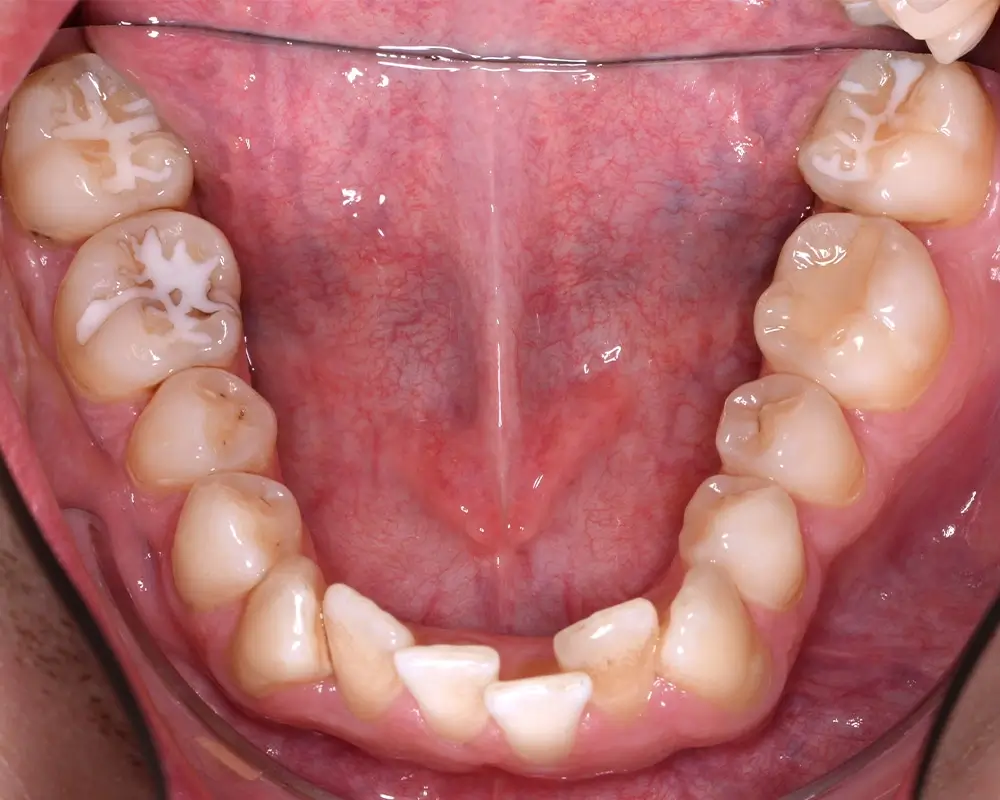

Кейс 4

Бажанова Ольга Валерьевна

Количество кап ВЧ 35

Количество кап НЧ 35

ДО

ПОСЛЕ